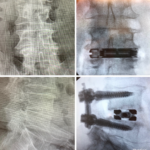

The dualX® LLIF solution is a comprehensive expandable interbody cage system for small portal access. dualX® LLIF is designed to minimize neural retraction while achieving maximum implant geometry.

The procedure is performed completely through an 18mm opening, reducing the potential psoas retraction up to 50%.

Vertical expansion assists in direct and indirect decompression

Heights 7mm* expanding to 17mm*

Width 13mm expanding to 22mm

Final Length 40 to 60mm

0°, 7°, 12° and 18° Lordosis*